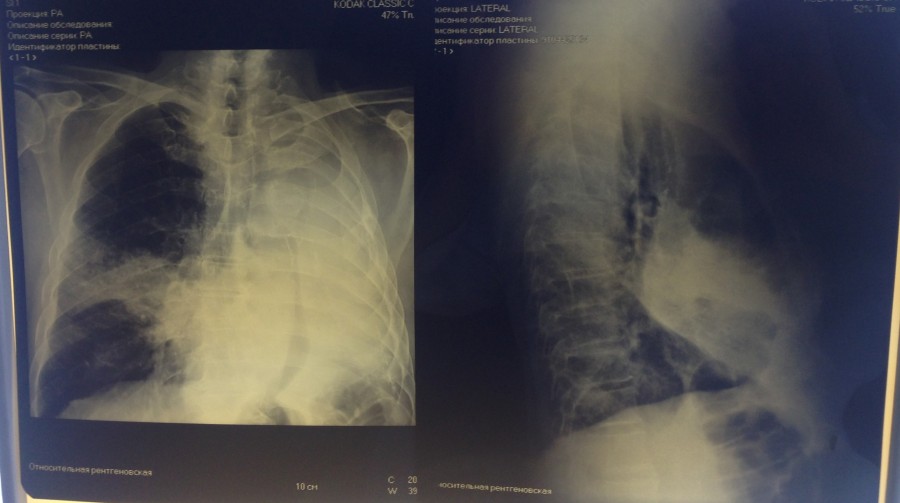

правосторонняя среднедолевая пневмония. Между снимками два дня.